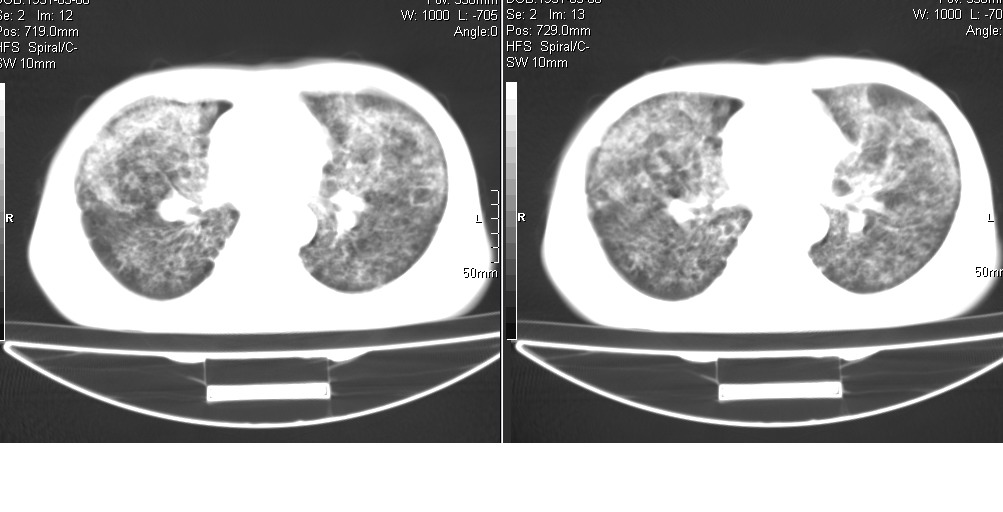

以下是引用光线在2008-5-6 18:36:00的发言:[br]双肺结核(左上肺空洞形成)、间质性改变合并感染,右肺大泡;右侧胸膜增厚。

以下是引用zsl6918在2008-5-7 1:54:00的发言:[br]首先肺泡蛋白质沉着症,其次考虑机遇性感染。